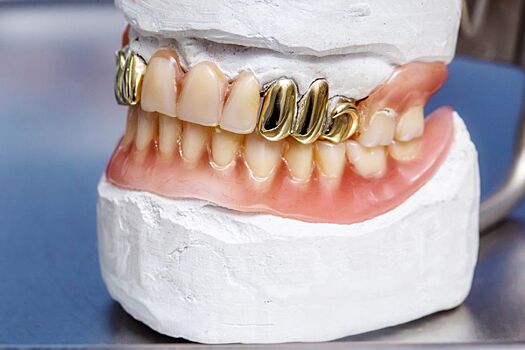

Укреплять зубы золотыми штампованными коронками не стоит, поскольку золото является мягким металлом и обладает рядом недостатков, которые приводят к многочисленным проблемам в полости рта. Об этом Агентству городских новостей «Москва» сообщил главный внештатный специалист - стоматолог министерства здравоохранения РФ, академик РАН, ректор Московского государственного медико-стоматологического университета им. А.Евдокимова Олег Янушевич. «Золото - довольно мягкий металл, и штампованные золотые коронки обладают множеством негативных свойств. Единственное преимущество золота - оно является инертным материалом, поэтому мало возникает проблем с аллергическими реакциями, непереносимостью. Однако данный материал быстро расходится, в эти места попадают микроорганизмы и остатки пищи. Как результат, коронки долго не существуют, а если и существуют, вокруг них возникают другого рода проблемы. Сейчас подобных штампованных коронок становится меньше, они уходят в небытие, и в целом мы рекомендуем их не применять», - сказал О.Янушевич. По словам стоматолога, в ближайшие годы золото продолжат применять в стоматологии в качестве сплавов для металлокерамических коронок, однако со временем врачи откажутся от этой идеи в пользу безметалловых конструкций. «Есть золотые сплавы и для металлокерамических коронок, и для многих других видов протезов. В этом случае материал тоже обладает определенной инертностью, но сверху покрывается керамикой. Это достаточно дорогие конструкции, и не все пациенты их могут позволить, но в целом спрос на них есть. В будущем керамика на золотых сплавах продолжит существовать, хотя, конечно, применять ее будут все реже. Данную методику через какое-то время вытеснит безметалловая керамика, на основе которой сейчас делают порядка 60% ортопедических конструкций», - пояснил О.Янушевич. Ранее директор Института стоматологии им. Е.Боровского Первого московского государственного медицинского университета им. И.Сеченова Ирина Макеева сообщила журналистам, что зубные коронки и протезы, выполненные из разнородных материалов, могут стать причиной развития злокачественных новообразований во рту человека.